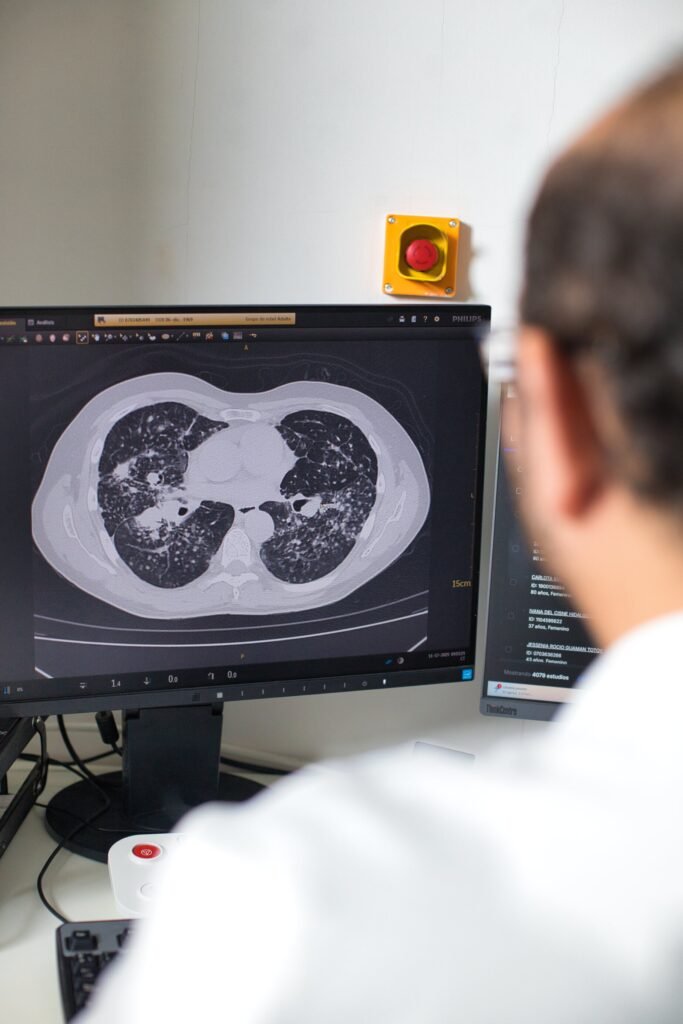

Tomografía

Philips Incisive CT de 128 detectores con reducción de dosis de radiación hasta un 80% y barridos ultra rápidos de 4 segundos .

Biopsias Guiadas por Tomografía de Pulmón

Obtención de muestras tisulares de nódulos y lesiones pulmonares sospechosas bajo visualización en tiempo real para diagnóstico histopatológico definitivo.